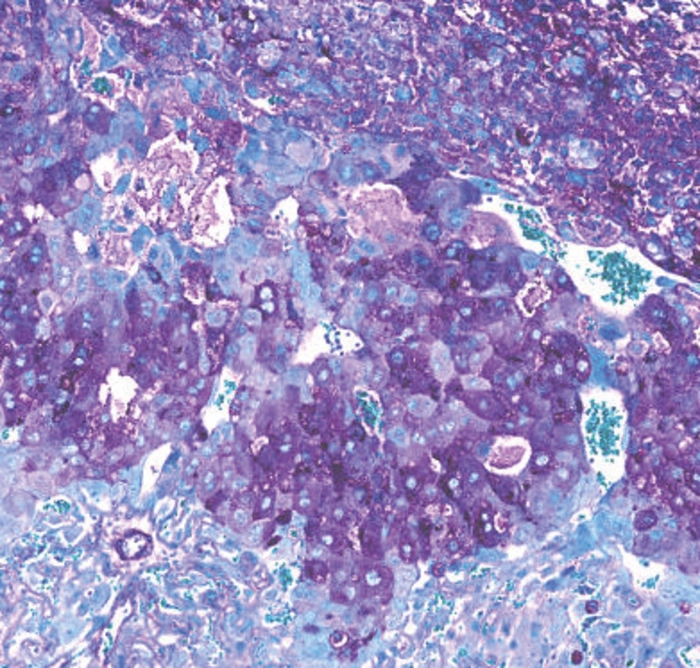

The mouse model study found that B. breve altered 150 biological processes, including 400 proteins, such as metabolism and cell cycle regulation.

Over 150 biological processes in the placenta, involving over 400 different proteins, were found to be different in mice with and without B. breve (Image credit: University of Cambridge).They add that the B. breve’s importance in mice is as relevant to human pregnancies as the bacteria. It is naturally found in the human gut, but levels of the bacteria could alter in pregnant women due to stress or obesity.